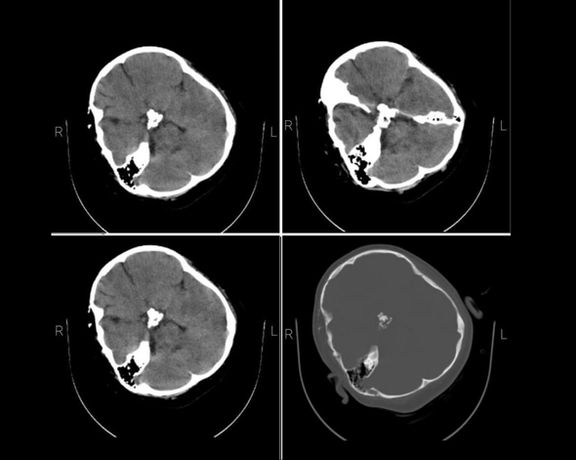

The skull CT scan of Mahsa Amini, the Iranian woman who died in religious police custody, shows bone fracture, hemorrhage and brain edema, Iran International has learned.

The medical documents and dozens of exclusive images sent to Iran International by a hacktivist group vividly show a skull fracture on the right side of her head caused by a severe trauma to the skull, which corroborate earlier accounts by her family and doctors about her being hit several times on the head, proving that the Iranian police's claim that she suffered a heart attack was untrue.